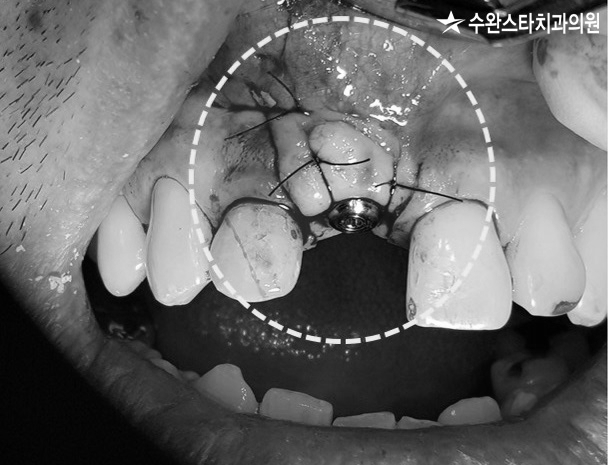

임플란트 식립 후 봉합, 40대 남성 (2022.08)

잘 봉합하여 마무리된 모습입니다.

잇몸 절개, 40대 남성 (2022.08)

건강한 잇몸이라면

임플란트가 안보여야 합니다.

하지만 환자분은 잇몸 뼈 부족으로 인해

임플란트가 훤히 다 보이고 있어

뼈 이식이 필요한 상태였습니다.

임플란트를 제대로 심기 위해선

해당 부위 치조골이

6~8mm 이상 되어야 하는데

이보다 얇은 경우

뼈이식을 통해 치조골 두께를

보강해 주어야 합니다.